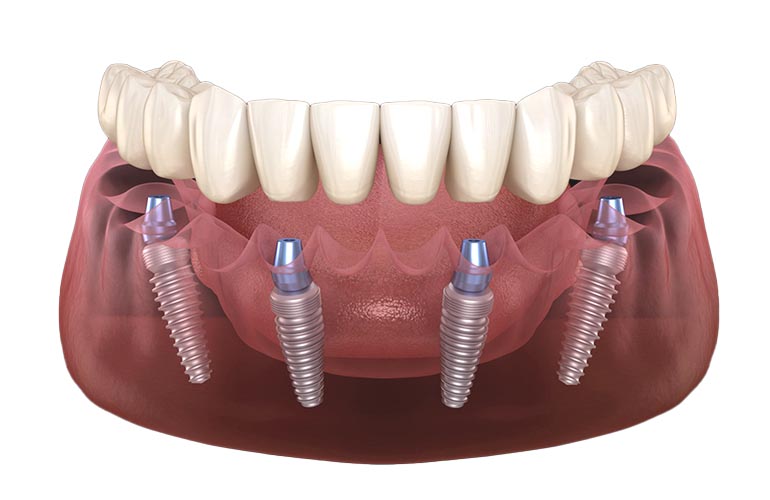

ALL ON 4

The All-on-4 treatment is a comprehensive solution for replacing a full arch of missing teeth using four strategically placed implants, providing stability, function, and aesthetics for a confident smile.